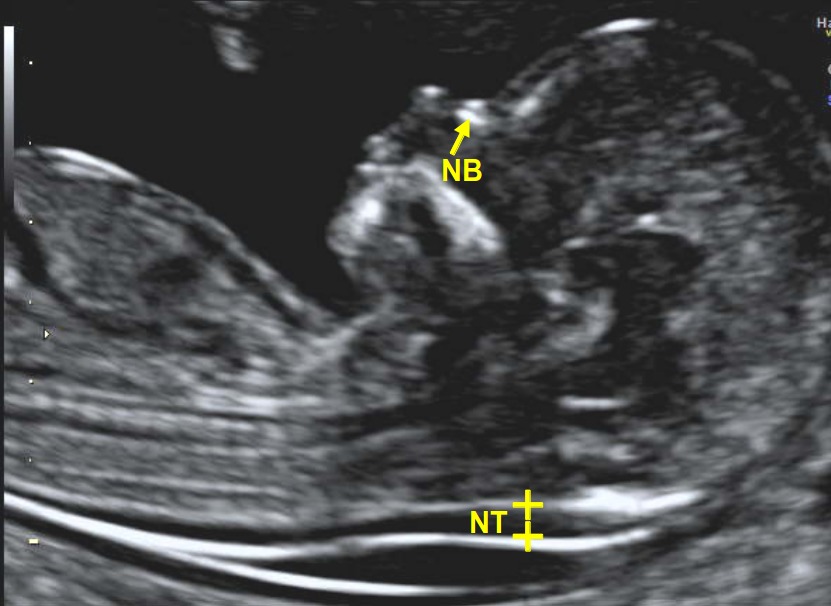

Aneuploidy/ Nuchal Translucency(NT) scan

Nuchal translucency scan is done around the 11th to 14th week of pregnancy. The scan aims to measure the size of the nuchal fold at the back of the baby’s neck to rule out the possibility or risk of any chromosomal abnormalities. With the help of a nuchal translucency scan, your health professional will rule out the risk of abnormalities like trisomy 21 (Down Syndrome), trisomy 18 (Edwards Syndrome), or trisomy 13 (Patau syndrome).